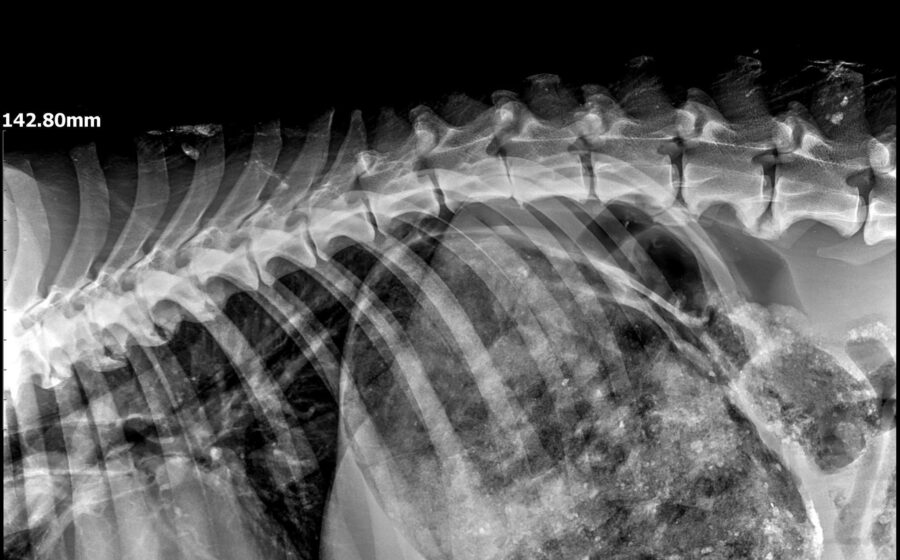

Völlig heruntergekommen, bis auf die Haut abgemagert und nicht mehr in der Lage zu laufen wurde Robinson unter einer Brücke gefunden. Hier hat er wohl schon längere Zeit hilflos gelegen. Robinson wurde in ein privates Shelter in Baia Mare gebracht und tierärztlich untersucht. Neben seinem katastrophalen Allgemeinzustand wurde eine Fehlstellung der Hinterbeine aufgrund von Mangelernährung festgestellt. Diese Fehlstellung scheint auch für seine Unfähigkeit zu laufen verantwortlich zu sein. Eventuell ist der arme Kerl auch inkontinent.